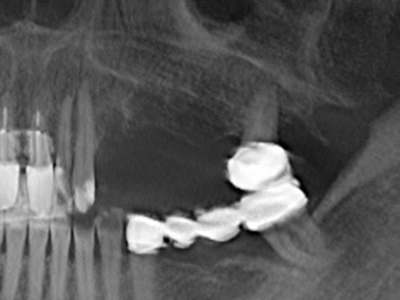

Indikation: Nervnahe Präparation

Wie bereits erwähnt lassen sich auch im Bereich der chirurgischen Zahnerhaltung Indikationsgebiete für die Piezochirurgie finden. Durch die Verwendung von speziellen Arbeitsspitzen wird die Darstellung der Wurzelspitze erleichtert, und gerade im unteren Prämolaren- und oberen Seitenzahnbereich lassen sich Nerven und Kieferhöhlenschleimhäute einfacher schützen. Bei undichtem apikalen Abschluss präparieren abgewinkelte Diamantspitzen zielgenau die Resektionskavität für das retrograde Wurzelfüllmaterial. Die Spitzen können durch die Ultraschalltechnik sehr grazil gestaltet sein, was Übersicht und Größe der Zugangskavität verbessert. So gehört in dieser Indikation die Anwendung der Ultraschallchirurgie zu den Standardverfahren der Wurzelspitzensresektion (Del Fabbro, Tsesis et al. 2010, Scarano, Artese et al. 2012).

Sollen chirurgische Eingriffe mit unmittelbarer Knochenbeziehung an empfindlichen Strukturen wie Blutgefäßen oder Nerven erfolgen, so bergen rotierende Instrumente ein erhebliches Potential an iatrogener Schädigung. Gerade bei Nervdarstellungen nach iatrogener Schädigung, oder aber im Zuge einer Nervlateralisation für resektive und rekonstruktive Eingriffe oder Implantatinsertionen können piezoelektronische Geräte hilfreich sein Knochendeckel zu präparieren und nervnahe Hartgewebsanteile zu entfernen (Abb. 17-20). Ein leichter Kontakt des Nervstrangs zur Piezospitze bleibt dabei in der Regel folgenlos – allerdings kann eine unvorsichtige Vorgehensweise mit sägeartigen Bewegungen bzw. Ansätzen bei noch vorhandener knöcherner Unterlage durchaus temporäre oder aber auch permanente Nervschädigungen verursachen. Das Risiko einer solchen Schädigung wird jedoch als wesentliche geringer eingeschätzt als unter Anwendung von Säge- oder Fräsinstrumenten (Pereira, Gealh et al. 2014).